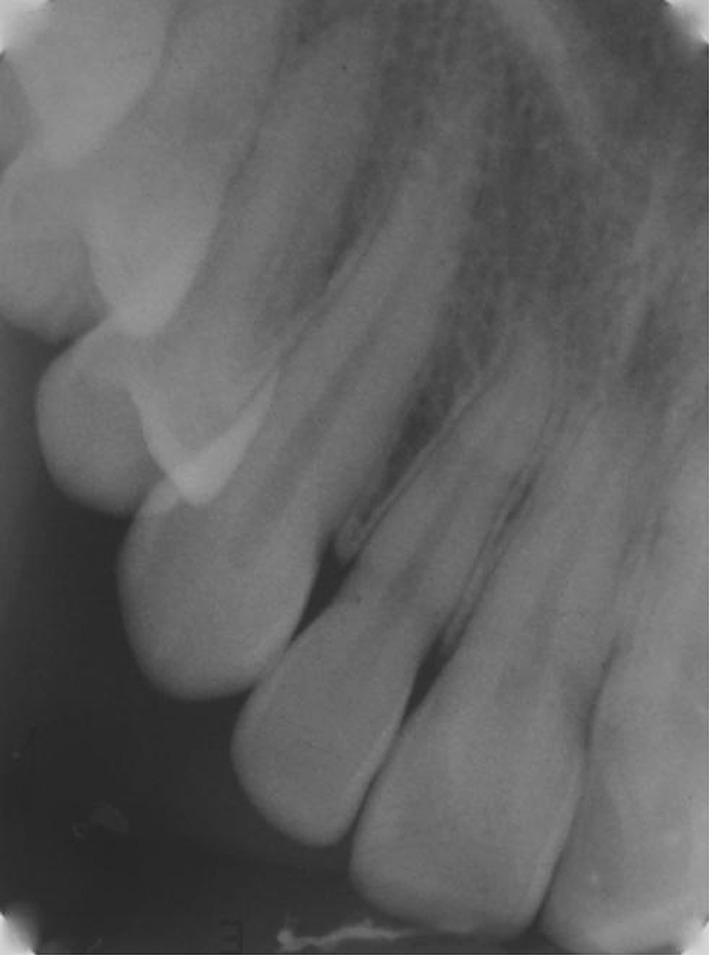

Fig. 17.

Post-distraction IOPA of PLD Side

Fig. 18.

Post-distraction IOPA of DAD Side